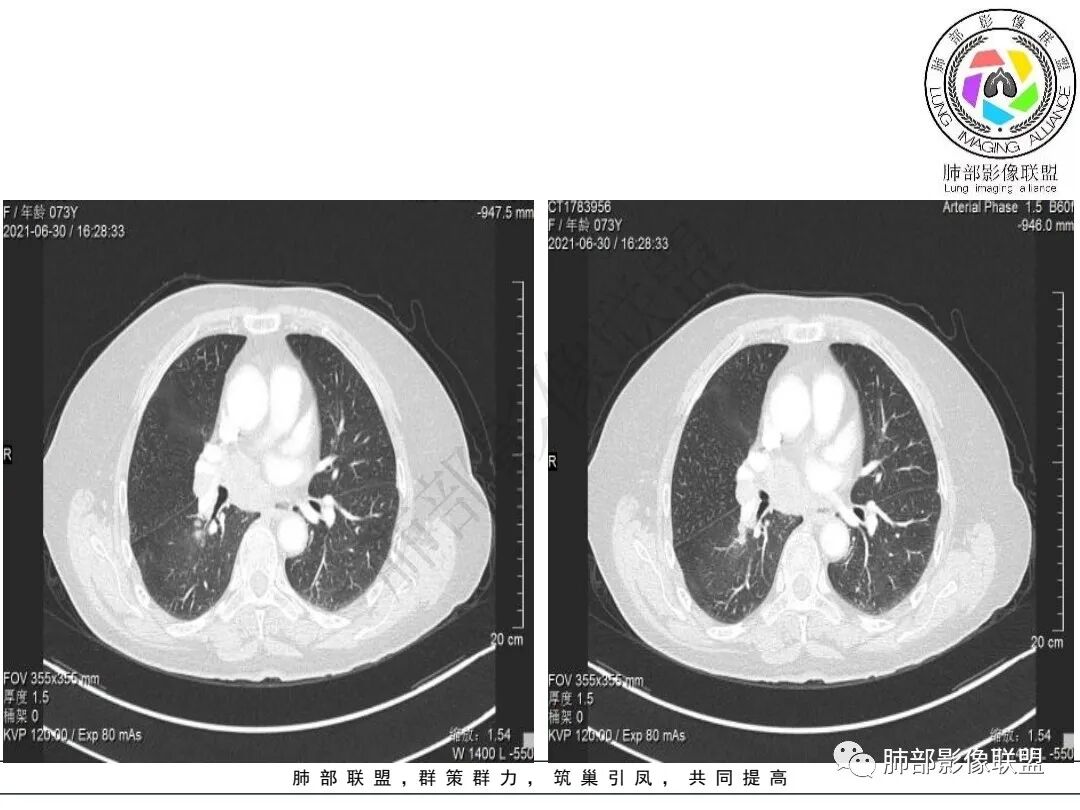

胸部CT:桶胸,肺气肿背景,右下肺不规则肿块影,沿支气管血管束生长,边界较清,边缘毛糙、锯齿样,基底干支气管腔内隆起,部分支气管进入后堵塞。平扫密度较均匀,轻度强化,肿块内血管增粗模糊,7区淋巴结肿大明显,内见小片坏死,左房受侵,邻近胸膜增厚。考虑恶性,低分化腺?鳞?鉴别TB、PC等。

2.右肺下叶不规则实性密度块影,占据外后基底段及背段较大范围,可见轻度分叶、毛刺及棘状突起,未见明显胸膜牵拉及凹陷。

3.右肺下叶支气管轻度狭窄,病灶内见部分充气支气管征,外后基底段不能连续跟踪。

4.右肺门及纵隔见多处增大淋巴结,不均匀环形强化,后下纵隔(隆突下)肿大淋巴结十分显眼!

1.老年女性,咳嗽两月。肺部明确块影,相应肺门及纵隔淋巴结肿大明显,怀疑肺部恶性肿瘤转移,影像学任务已基本。

1)女性不吸烟患者,病灶虽强化不显著,但未见大范围坏死或空洞,肺鳞癌的可能性较小。

2)块影收缩乏力,强化不显著,不是典型的肺腺癌影像学表现。

3)病灶强化不显著,支气管相关,纵隔淋巴结肿大明显,小细胞癌的可能性是比较大的。黄勇老师曾统计后下纵隔(隆突下)显著肿大淋巴结,小细胞癌占比相当高,临床实践也是如此。

4)应当排除的还有粘液表皮样癌、腺样囊性癌、淋巴上皮瘤样爱、混合癌等等……